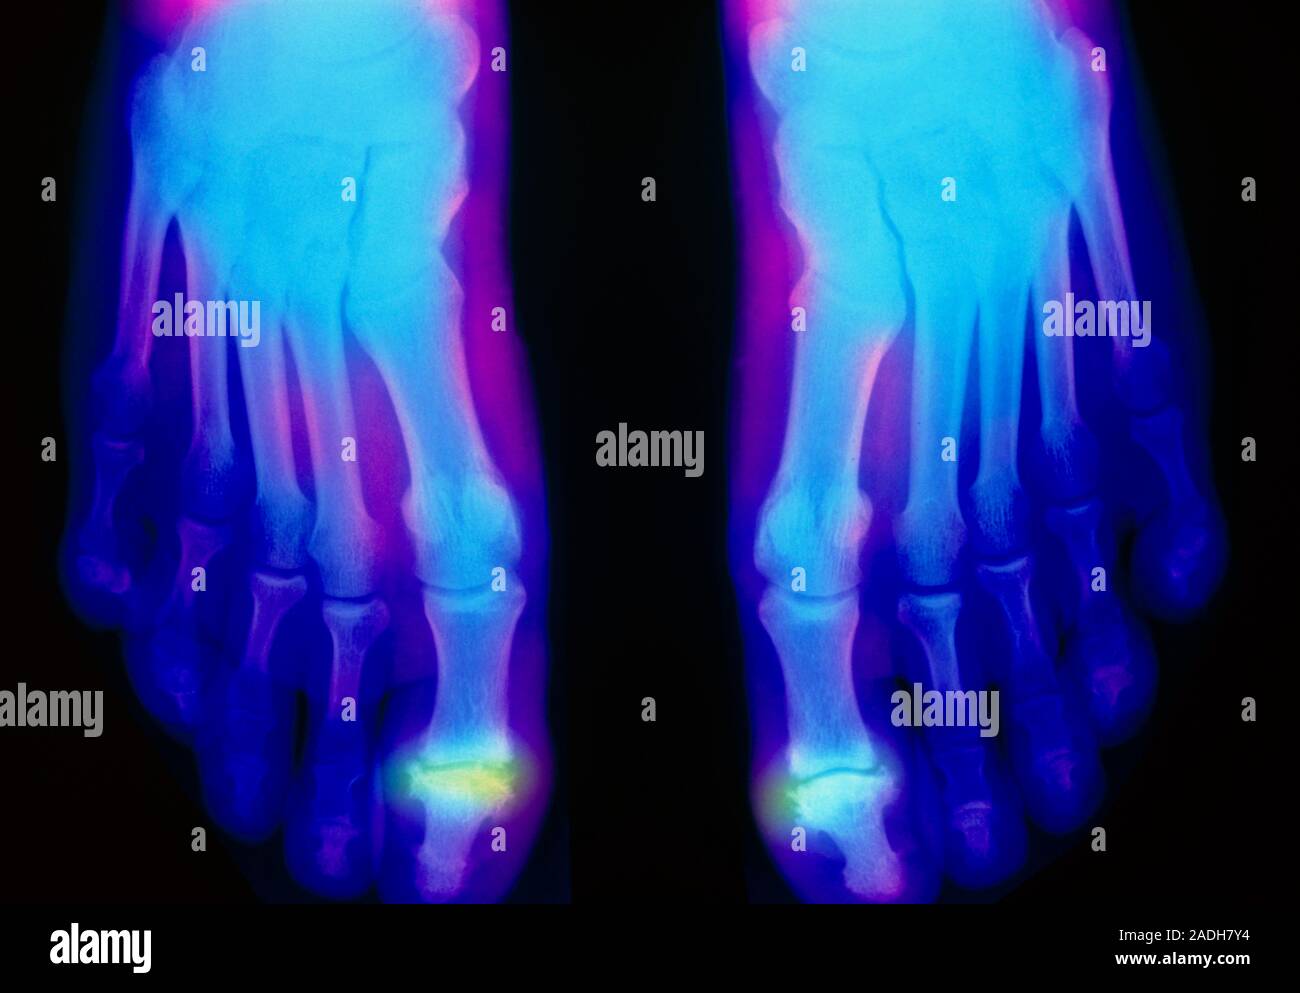

From www.alamy.com

Rheumatoid arthritis. Falsecolour Xrays showing destruction of the toe joints in both feet due Rheumatoid Arthritis Big Toe Joint ra is an autoimmune disease that causes inflammation and damage in the joints, including the toes and feet. hallux rigidus means “stiff big toe” — the condition’s most common symptom. Hcp support & resourcesdosing & admin info an autoimmune disorder, rheumatoid arthritis occurs when your immune system mistakenly attacks your own body's tissues. Many of these issues. Rheumatoid Arthritis Big Toe Joint.